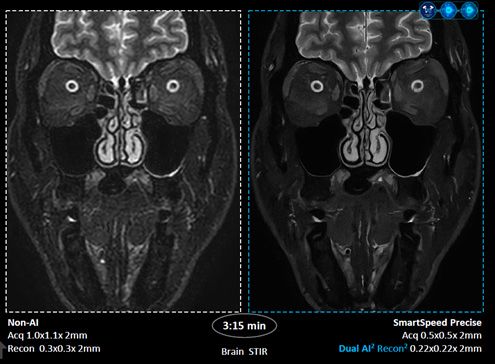

스마트스피드 프리사이즈는 필립스의 기존 MR 검사 시간 단축 기술 ‘컴프레스드 센스(Compressed SENSE)’에 듀얼 AI 엔진을 적용한 것이 특징이다. 데이터 밸런싱 알고리즘과 AI 재구성 알고리즘을 원시 데이터 단계부터 적용해 핵심 신호만 선별하고 불필요한 노이즈를 제거한다.

회사에 따르면, 이 기술은 기존 대비 최대 3배 빠른 검사 속도를 구현하면서도 영상 선명도를 최대 80%까지 높인다. 초고해상도 알고리즘을 강화해 신호대잡음비(SNR)를 개선하고, 링잉 방지 기능을 더해 영상 품질을 향상시켰다는 설명이다.